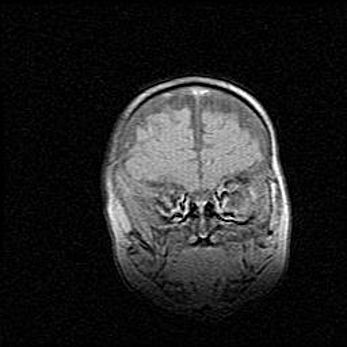

Мальформация Денди-Уокера. Киста задней черепной ямки.

Агенезия мозолистого тела.

Возраст: 2,5 месяца

Вес: 2420 г

Пол: женский

Окружность головы: 37 см

Срок гестации: 32 недели

Мальформация Денди—Уокера — редкий вид патологии ЦНС, представляющий собой врожденный порок развития каудального отдела ствола и червя мозжечка, ведущий к неполному раскрытию срединной (Мажанди) и латеральных (Лушка) апертур IV желудочка мозга. Для этогно синдрома характерна триада симптомов: гипотрофия червя мозжечка и/или полушарий мозжечка, кисты задней черепной ямки, гидроцефалия различной степени. В 70% случаев порок сочетается и с другими аномалиями головного мозга, в частности с агенезией мозолистого тела.